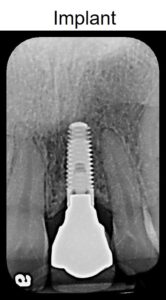

Dental implants consist of three major components: the implant itself, which is inserted directly into the jawbone, the abutment which connects the implant to the third component, the dental crown. The latter is the only visible portion of the implant assembly, once the restoration has been completed.

Multiple factors can affect the survival of dental implants, including where the implant is placed, bone quality, and the diameter and length of the implant [1]. With these factors in mind, here are a few reasons why some dental implants last longer than others.